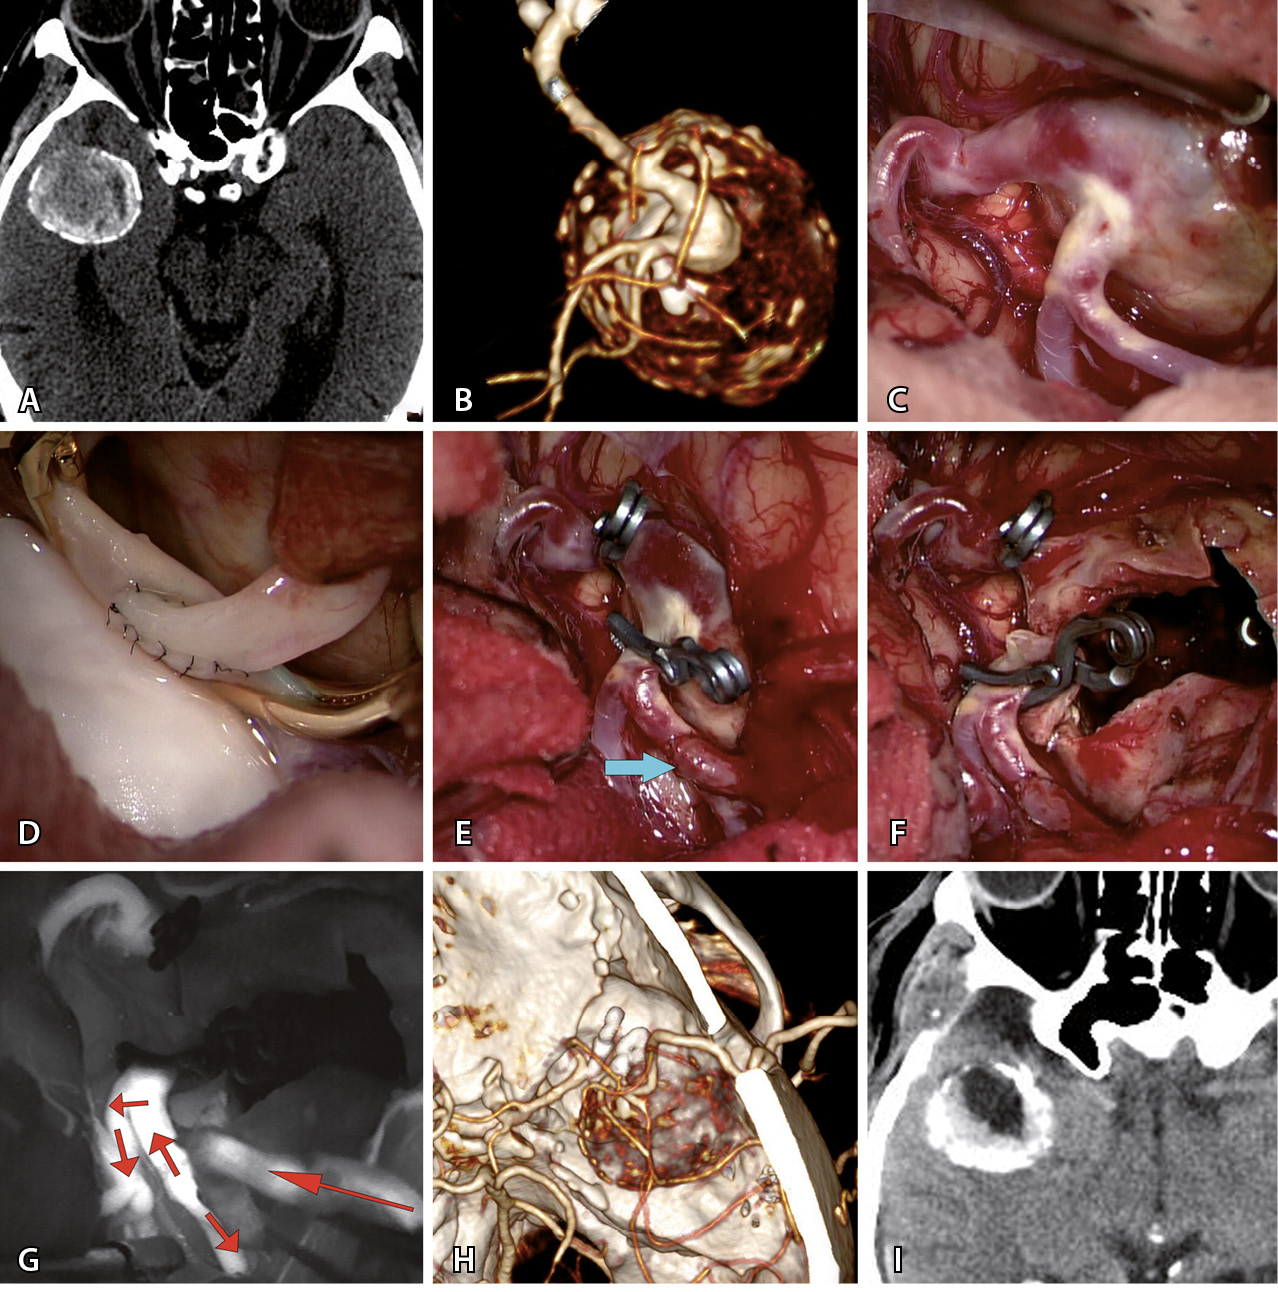

Наиболее частой операцией было клипирование шейки (КШ) – в половине (50,9%) всех случаев. Клипирование аневризмы одной клипсой произведено только в 5 наблюдениях. У остальных 23 пациентов выполнено множественное клипирование с наложением от 2 до 7 клипс (в среднем – 3,2 ± 1,5). Пример клипирования гигантской аневризмы приведен на рис. 1. У 17 больных перед КШ проведена тромбэктомия из полости гигантской аневризмы. У 6 больных тромбэктомию делали после КШ.

Рис. 1. Клипирование гигантской аневризмы средней мозговой артерии (СМА) справа у пациентки Г., 59 л. А – при компьютерной томографической ангиографии определяется гигантская аневризма трифуркации СМА справа (желтыми стрелками указаны три М2-ветви СМА справа, белой стрелкой указана припаянная к телу аневризмы передняя височная артерия). Б – интраоперационное фото: отмечается выступающее в сильвиеву щель тело аневризмы СМА справа. В – после наложения временной клипсы на М1-сегмент справа (указан черной стрелкой) мешок аневризмы релаксировал, что позволило выделить и визуализировать три М2-ветви (указаны желтыми стрелками). Г – длинная изогнутая клипса наложена на шейку аневризмы. Д – после клипирования наблюдается небольшой остаточный участок шейки аневризмы (указан стрелкой) у теменного М2-сегмента. Е – наложение на остаточный участок шейки аневризмы маленькой изогнутой клипсы. Ж – результат клипирования шейки аневризмы двумя клипсами. З – контрольная церебральная ангиография в прямой проекции. И – контрольная церебральная ангиография в боковой проекции

Операции с созданием байпаса сделаны в 19 случаях. Байпас перед треппингом аневризмы выполнен у 10 пациентов (в 8 случаях после треппинга проведена тромбэктомия). В 3 случаях при фузиформных гигантских аневризмах проведено проксимальное клипирование с целью создания возможности ретроградного кровоснабжения ветвей, выходящих из аневризмы. У 4 пациентов была реваскуляризация одной из М2-ветвей, где гигантская аневризма клипирована вместе с устьем данной ветви. В 2 случаях потребность в анастомозе возникла как экстренная мера вследствие тромбоза одной из ветвей СМА после КШ. Наиболее частым (n = 15) байпасом был микроанастомоз между М2–М4 ветвью СМА и поверхностной височной артерией (ПВА). Пример представлен на рис. 2. Микроанастомозы с двумя ветвями ПВА выполнены в 6 случаях. Высокопоточный байпас между наружной сонной артерией и М2-сегментом СМА с использованием графта лучевой артерии выполнен в 3 случаях при гигантской аневризме М1-сегмента. В 1 наблюдении произведена местная реимплантация одной М2-ветви в другую.

Рис. 2. Треппинг с тромбэктомией гигантской фузиформной частично тромбированной аневризмы М2-сегмента средней мозговой артерии (СМА) после создания экстра-интракраниального микроанастомоза у пациента Т., 69 л. А – компьютерная томография до операции: определяется гигантская частично тромбированная аневризма правой СМА. Б – компьютерная томографическая ангиография (3D) до операции: видна функционирующая часть фузиформной частично тромбированной аневризмы М2-сегмента правой СМА. В – интраоперационное фото: вид аневризмы после препаровки сильвиевой щели. Г – анастомоз между поверхностной височной артерией и М2-сегментом СМА. Д – треппинг аневризмы (стрелкой указан анастомоз). Е – вид аневризмы после тромбэктомии из ее полости. Ж – флюоресцентная видеоангиография: видно хорошее контрастирование шунта через анастомоз и заполнение М2-ветвей (стрелками указано направление кровотока). З – компьютерная томографическая ангиография (3D) после операции: аневризма не контрастируется и хорошо заполняется экстра-интракраниальный анастомоз. И – компьютерная томография головы после операции